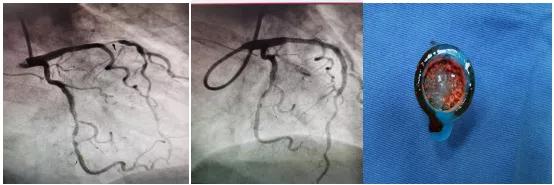

术中发现患者左冠状动脉前降支近段95%弥漫性狭窄,可见血栓影,中段80%节段性狭窄,远端80%节段性狭窄,考虑为急性左冠脉前降支近段病变为罪犯病变,王健副主任立刻提出:运用血栓抽吸装置对该部位进行血栓抽吸。随后,抽吸出大量红白色血栓,并为患者进行药物球囊扩张。

术后患者恢复良好,继续规范药物治疗,实现了急性心肌梗死患者“有介入、无植入”的最好结果。